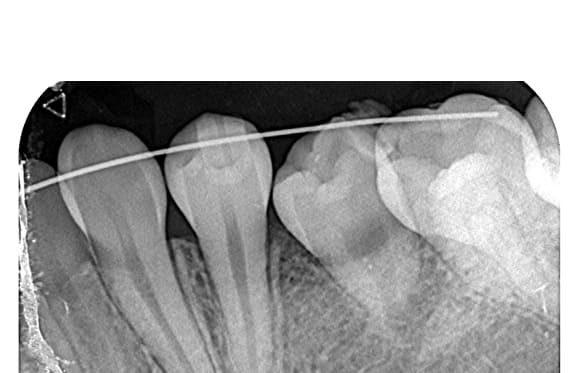

根管内の破損器具除去

● 症例1

01 左下7の近心根にエンジンファイルの破折

02 ファイル除去時

※根尖周囲の透過像はまだ残存

03 最終の根充剤を充填

※根尖透過像が小さく治癒方向へ向かっている